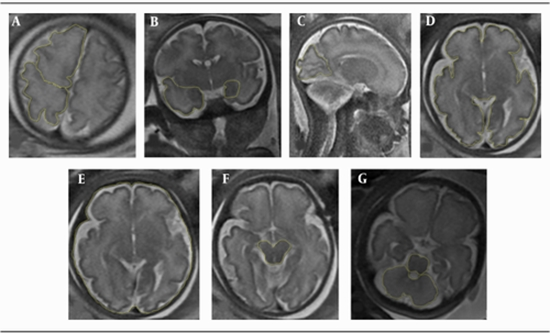

Forty-two women with IUGR pregnancy and 28 women with normally grown fetuses at 28 - 38 weeks of pregnancy underwent 3-tesla magnetic resonance imaging (MRI). Cortical thickness was assessed in four regions and corrected by the biparietal diameter/2. Also, the whole brain surface area (WBA) was measured, and the areas of six brain regions were calculated and corrected by WBA.Results:

In the IUGR group, the cortical thickness in the insula and temporal lobe was significantly thinner than the control group (0.034 vs. 0.043 and 0.036 vs. 0.047, respectively; P < 0.05); these fetuses also showed significantly reduced WBA (P = 0.028). The corrected brain areas were not significantly different between the groups, except for the corrected areas of the cerebellum and the hippocampus, which increased in the IUGR group as compared to the control group (0.147 vs. 0.130 and 0.017 vs. 0.0125, respectively; P < 0.05).Conclusion:

In the IUGR fetuses, significantly thinner insular cortex and temporal lobe cortex and smaller WBA were found compared to the control group. Among different brain regions, the cerebellum and the hippocampus were less affected by growth restriction in the antenatal period